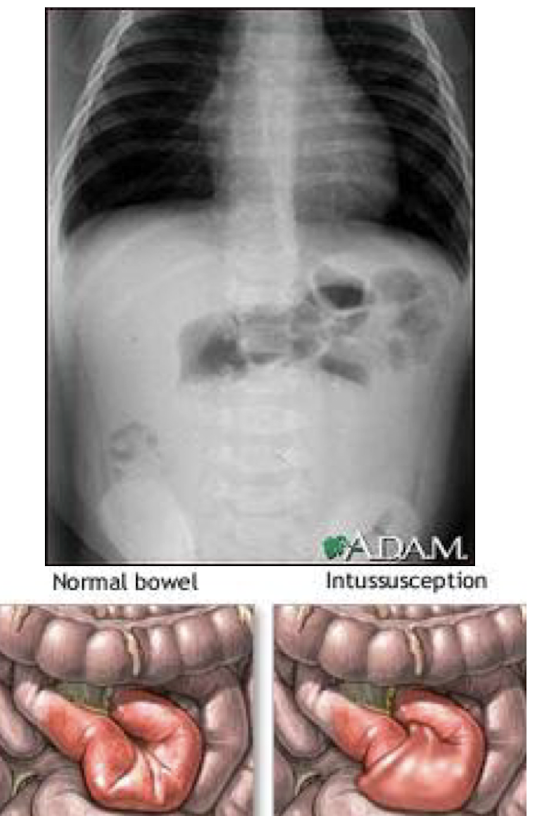

What is intussusception

A condition where a part of the intestine telescopes into an adjacent segment, causing obstruction and potential ischemia.

How is the diagnosis of intussusception confirmed and treated at the same time?

Diagnosis is typically confirmed through an abdominal ultrasound or CT scan, and treatment is performed via an air contrast enema or surgical intervention.